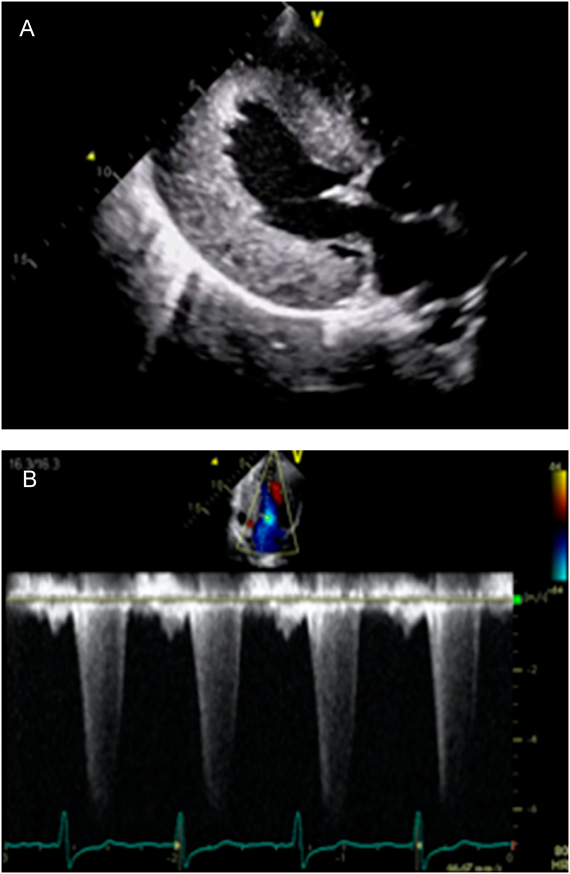

The patient is a 19-year-old Japanese man. He was born to non-consanguineous parents at the gestational age of 38 weeks. At the age of 2 days, a heart murmur was observed. He was transferred to our hospital for further investigation. Clinical examination revealed facial dysmorphism with widely spaced eyes and low-set ears. We performed echocardiography, which revealed significantly thickened left ventricular posterior wall (LVPW) and interventricular septal thickness (IVST). The measurements of IVST and LVPW at the end-diastolic phase were 12.2 and 11.9 mm, respectively. Severe LVOTO was also noted with a peak pressure gradient of 93 mmHg. We diagnosed the patient as having Noonan syndrome based on clinical manifestations. LVOTO was severe, however, there were no symptoms of heart failure; therefore, the patient was managed regularly on an outpatient basis. Although the patient had no subjective symptoms, LVOTO remained severe. We started propranolol administration when the patient was 5 years old. However, there was no significant change in the echocardiography parameter. His lentigines were not particularly noticeable in early childhood, but the number of lentigines increased with his growth. Based on clinical symptoms, we suspected the patient of having NSML. To confirm, we conducted a genetic testing at the age of 12 years and observed a heterozygous missense mutation NM_001330437.2: c.1528C>G (p.Q510E) in exon 13 of the PTPN11 gene that was previously reported in patients with NSML.8) The patient had no complaints and was able to live his daily life without any symptoms. However, if this condition is left untreated, sudden death from a fatal arrhythmia may occur. Surgical intervention had to be considered, however, both parents and patient were reluctant to perform highly invasive surgical treatment. Therefore, we decided to perform treatment using an mTOR inhibitor, rapamycin analog, sirolimus. We initiated sirolimus treatment when the patient was 19 years old. Treatment began after approval by the ethics committee of St. Marianna University (IRB approval #3522), and a written informed consent was obtained from his parents. The dose of sirolimus was determined with reference to the dose used for lymphangioleiomyomatosis and was scheduled to be taken daily (1 mg/day) for 16 weeks. To confirm the efficacy of the treatment, blood test, electrocardiogram, chest X-ray, and echocardiography were performed 2, 4, 8, 12, and 16 weeks before and after sirolimus administration. Echocardiography performed before sirolimus treatment showed significantly thickened entire left ventricular wall. IVST, left ventricular internal dimension (LVID), and LVPWT at the end-diastolic phase were 19, 40, and 21 mm, respectively. The calculated peak pressure gradient of LVOTO was 136 mmHg. In tissue Doppler method, both e′ septal and e′ lateral were slightly low with 3.6 cm/s and 3.1 cm/s, respectively, and the calculated average E/e′ was as high as 28.6, which suggested a decrease in the LV diastolic function and an increase in the left atrial pressure (Fig. 1A, B). Chest X-ray examination showed cardiomegaly with a cardiothoracic ratio of 60% without pulmonary congestion. Electrocardiographic findings were suggestive of severe left ventricular hypertrophy and myocardial damage, such as left axis deviation, high RV5 potential, and negative T wave at V4–6. Brain natriuretic peptide (BNP) level was significantly elevated to 3,495.6 pg/mL. Other blood test data were within the normal range. The echocardiographic measurements of the end-diastolic phase, IVST, LVD, LPWT, peak pressure gradient of LVOT, tissue Doppler measurements of e′ septal, e′ lateral, and E/e′, and BNP changes are shown in Fig. 2A–D. BNP level decreased after administering sirolimus; however, the data at 16 weeks after the start of administration were almost equal to the data before administration. No major changes were observed in the values measured using echocardiography and tissue Doppler method.

Fig. 1 Severity of left ventricular thickening and left ventricular outflow tract obstruction on echocardiography

A: Echocardiography showed significantly thickened wall of the entire left ventricle. IVST and LVPWT at the end-diastolic phase were 19 mm and 21 mm, respectively. B: Calculated peak pressure gradient of the LVOT by tissue Doppler method was 136 mmHg. IVST, interventricular septum thickness; LVOT, left ventricular outflow tract; LVPWT, left ventricular posterior wall thickness.